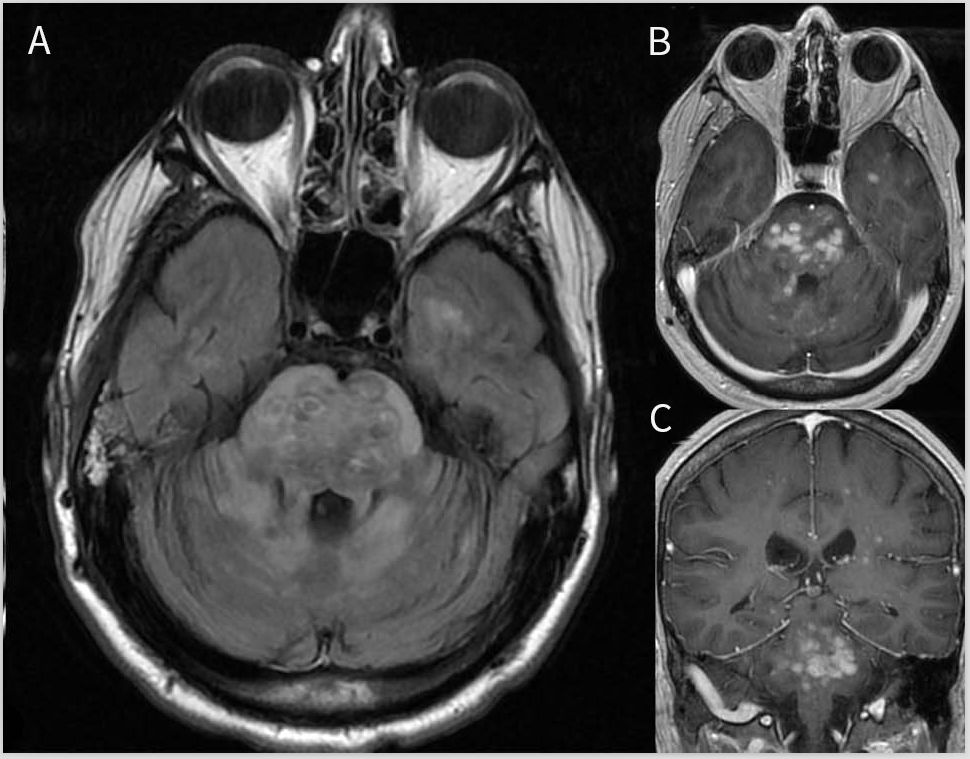

在27%的LCH患者的MRI中可见脑干受累,通常与齿状核和白质受累同时发生,冠状位可见蝴蝶翅征。在脑桥锥体束或被盖白质中可见斑片状T2高信号病灶,可出现斑驳状外观,蔓延至小脑脚(图7)。LCH和CLIPPERS的MRI表现可能非常相似,但LCH往往具有较大的结节,T2高信号病灶范围比T1强化病灶更大;还可见增大的血管周围间隙、实质强化和弥漫性白质脑病。

图7 朗格汉斯细胞组织细胞增生症患者MRI影像。轴向FLAIR(A)显示脑桥和邻近的小脑半球弥漫性和不均匀性高信号,呈斑驳的外观。轴位(B)和冠状位(C)T1增强图像可见脑桥病灶呈斑点状强化。